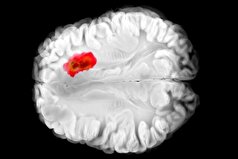

تشخیص زودهنگام سرطان ریه از طریق آزمایش خون

به گزارش مجله خبری نگار، شرکت هیدروگراف کلین پاور اعلام کرده است که محصول گرافن پرچمدار آنها موسوم به FGA-۱ با موفقیت در زیستحسگرهای پزشکی شرکت هاوکی بیو (Hawkeye Bio) مورد استفاده قرار گرفته است. هدف از ساخت این حسگرها، تشخیص زودهنگام سرطان ریه است.

دلیل استفاده از گرافن شرکت هیدروگراف کلین پاور توسط هاوکی بیو، خلوص و کیفیت گرافن این شرکت است. هاوکیبیو، یک شرکت فناوری پزشکی مستقر در لسآنجلس است که حسگری ساخته که فعالیت آنزیمها را تشخیص داده و با این کار امکان تشخیص بهتر بیماریهای التهابی مزمن مانند سرطان یا خود ایمنی را امکانپذیر میکند. این حسگر همچنین با استفاده از نمونه زیستی که به صورت غیر تهاجمی از بدن گرفته میشوند، مانند خون، ادرار، بزاق یا بازدم، از آنها برای انجام آزمایش سرطان ریه در مراحل اولیه، استفاده میکند.

به گفته مدیرعامل شرکت هاوکیبیو، از گرافن هیدروگراف کلی پاور برای تولید زیستحسگرها به منظور تشخیص سرطان ریه استفاده میشود. فرآیند تولید هیدروگراف کلین پاور به طور تکرار شونده امکان تولید محصول با خلوص ۹۹٫۸ درصد را فراهم کرده که از نظر شکل هندسی نیز به گونهای است که میتوان از آن برای تشخیص بیماری استفاده کرد. عملکرد بهینه سیگنال به نویز گرافن در این زیستحسگر به آن اجازه میدهد تا آزمایش خون در مراحل بسیار اولیه سرطان ریه بتواند فرآیند تشخیص را انجام دهد.

این حسگر تغییرات پیچیدهای در آنزیمها را ردیابی میکند و با این کار حساسیت از واکنش زنجیرهای پلیمراز (PCR) نیز بیشتر میشود و همچنین از نظر سهولت کاربرد از ایمونوسوربنت مرتبط با آنزیم ELISA مطلوبتر است. از نظر عملکرد نیز این حسگر نانویی بهتر از توالییابی نسل بعدی (NGS) بوده و هزینه آن بسیار کمتر است.

به نقل از ستاد نانو، هیدروگراف کلین پاور، گرافن و مواد دیگر را با استفاده از فناوری خود یعنی سیستم انفجار هایپریون، تولید میکند. این فناوری برای مقیاس تجاری ایدهآل است. شرکت هیدروگراف کلین پاور بهطور فعال فرآیند اختصاصی و انحصاری خود را برای تولید گرافن، هیدروژن و سایر مواد راهبردی با قیمتی رقابتی و اثرات منفی زیستمحیطی اندک تجاریسازی کرده است.